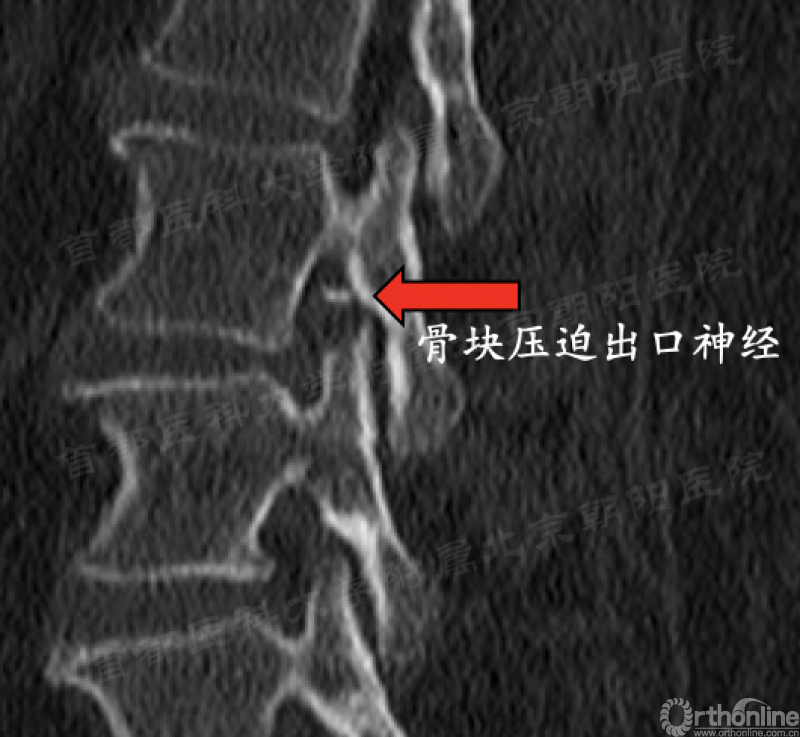

b. 第91例,第一次神经损伤,也希望是最后一例。

第91例,L2/3节段I-2-a区LDH。在置管后患者诉左下肢屈髋较对侧无力,无下肢放射痛及麻木,术中透视如图(红框)所示。镜下摘除髓核后将工作通道朝向背侧观察神经,患者诉颈部疼痛(脊髓高压症),镜下发现硬膜缺损(红箭头),但神经结构完整。立即结束手术。术后髂腰肌肌力IV级,大腿前方感觉减退,术后复查CT显示L3上关节成型后游离骨块导致出口神经受压。

总结教训:

1、L2/3以上节段穿刺点尽量靠内,不可将工作管道一次性置入椎管;

2、术中患者一旦出现神经症状应立即调整;

3、患者诉颈部疼痛,不是“趴着累了”,应考虑硬膜缺损,脊髓高压,需立即停止手术,必要时对症治疗;

4、在行关节突成型时应警惕尖部骨块游离挤压出口神经的可能性。